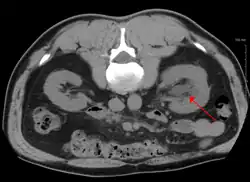

Left sided hydronephrosis in a person with an atrophic right kidney. Stent is also present (image below).

Left sided hydronephrosis, coronal view. Stent is also present.

Treatment of hydronephrosis focuses on the removal of the obstruction and drainage of the urine that has accumulated behind the obstruction. Therefore, the specific treatment depends upon where the obstruction lies.[14]

Acute obstruction of the upper urinary tract is usually treated by the insertion of a nephrostomy tube. Chronic upper urinary tract obstruction is treated by the insertion of a ureteric stent or a pyeloplasty.[13]

Lower urinary tract obstruction (such as that caused by bladder outflow obstruction secondary to benign prostatic hyperplasia) is usually treated by insertion of a urinary catheter or a suprapubic catheter. Surgery is not required in all prenatally detected cases.[21]